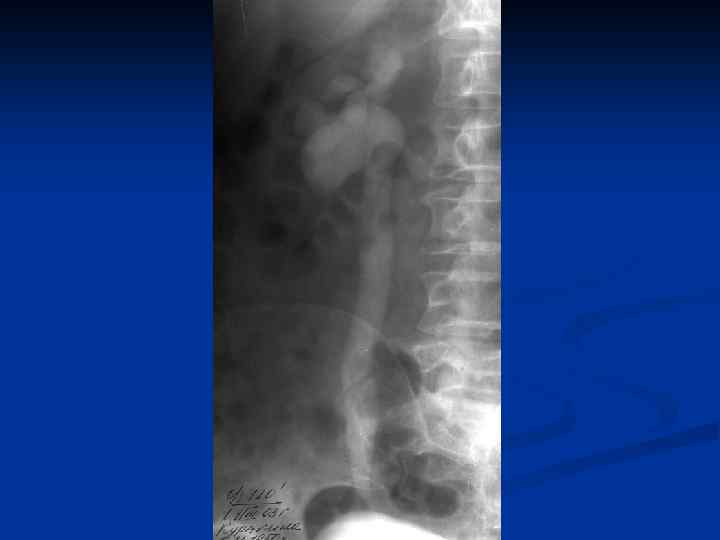

n n n Провести рентгеновское исследование грудной клетки, а если есть показания, то и других органов; Определить туберкулиновую чувствительность; Назначить и провести гистеросальпингографию с 60% раствором водорастворимого верографина, при этом возможно: n n n Определить состояние маточных труб (тонкие, ригидные, запаянные ампулярные отделы, деформация в виде четок, курительных трубок); Выявить форму полости матки, ее размеры, наличие или отсутствие сокращений; Диагностировать наличие / отсутствие рефлюкса контрастного вещества из труб.